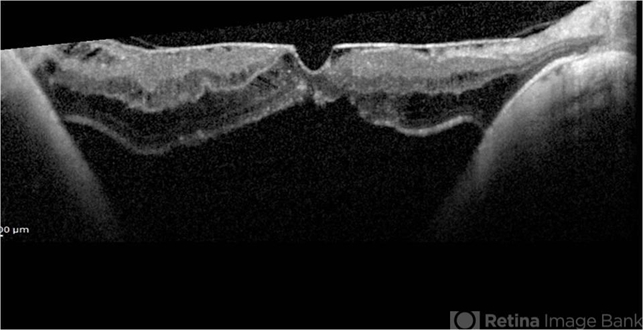

- high myopia, posterior staphyloma, macular detachment, pathologic myopia, myopic traction maculopathy

- Spectral domain optical coherence tomography of macular detachment in posterior staphyloma - myopic traction maculopathy (MTM).